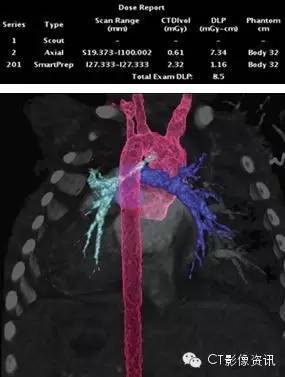

Case 2 主动脉肺动脉共干 女,3 月。 先天性心脏病,临床听诊心脏杂音。

扫描协议 探测器宽度:120mm, Axial; 管电压和管电流:70kV, SmartmA; 旋转速度:0.28s/rot;迭代:ASiR-V 70%; 身高:52cm;体重:4.0kg; 对比剂:270mgI/ml, 6ml, 0.6ml/s; 扫描剂量:0.10mSv。

点评 仅见一粗大动脉干,骑跨率约75%(大部分起自右心室)。动脉干近段左侧壁,发育好,直径约10mm。主动脉升弓部发出左肺动脉,近段节段性重度狭窄,最窄处直径约 1.3mm。

临床小知识 肺动脉发自右心室,如果肺动脉从主动脉发出,称共干畸形,根据发出部位肺动脉的情况进行分型,通常预后较差。